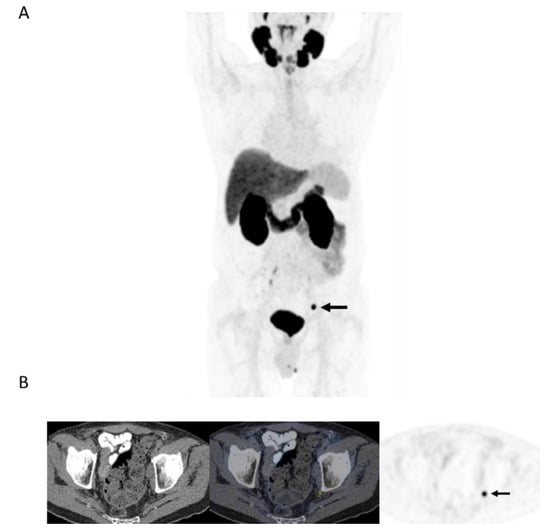

Figure 3.

78-year-old man 4 years after radical prostatectomy for pT3a N0 adenocarcinoma of prostate ISUP Grade Group 3. Now biochemical recurrence (serum PSA = 0.80 ng/mL); PET performed prior to salvage prostate bed radiotherapy. (A) MIP PET image showing solitary focus of abnormal tracer uptake in the pelvis on the left. (B) Axial PET/CT image (CT–left; fused PET/CT–middle; PET–right) shows an intensely 18F-DCFPyL-avid 0.3 cm left pelvic sidewall lymph node (SUVmax = 25.6; PSMA score, 3), in keeping with a metastatic node. After PET, the patient was treated with PET-directed stereotactic radiotherapy with favorable metabolic response (>76% decrease in serum PSA).

Overall, (13/29) 44.8% of patients without extensive metastases on PET were treated with PET-directed focal ablative therapies without systemic therapy (Figure 3). The mean PSA response to focal ablative therapies was 69% (median, 74.5%; range: 35–100). Favorable biochemical response (>50% drop in pre-PET PSA) was observed in 10/13 (76.9%) patients with limited recurrence on PET, and in 3/13 (23.1%), there was complete biochemical response.

Our initial experience with PSMA PET in the workup of patients with biochemical failure after primary therapy for prostate cancer with no definitive metastatic disease on conventional workup has shown PSMA PET positivity in more than 90% of patients, with local recurrence or oligometastatic disease in over half of them. Tumor detection rate in our cohort (with median serum PSA of 3 ng/mL) are in line with those reported in the previous prospective CONDOR trial in which disease detection was 73.3% when serum PSA was <0.5 ng/mL and rose to 96.4% when serum PSA was >5 ng/mL [9]. More than 40% of the patients with limited recurrence were treated with PET-directed ablative therapies to sites of disease without systemic therapy, and the biochemical response was favorable in more than 3 in 4 of them (Figure 3). Overall, in more than 20% of patients in this study (10/47) with biochemical failure and no conventional workup evidence of recurrent disease, PET identified limited recurrence amenable to focal ablative therapies with a favorable biochemical response (>50% drop in serum PSA). In nearly a quarter of patients treated with limited ablative therapies, there was complete biochemical response to therapy. These findings are in line with a prior prospective trial that included 72 patients in whom 38 were treated for oligorecurrent prostate cancer amenable to metastasis-directed therapy. Overall response rate in that study was 60%, including 22% with complete biochemical response at a median follow-up of 15.9 months [10].